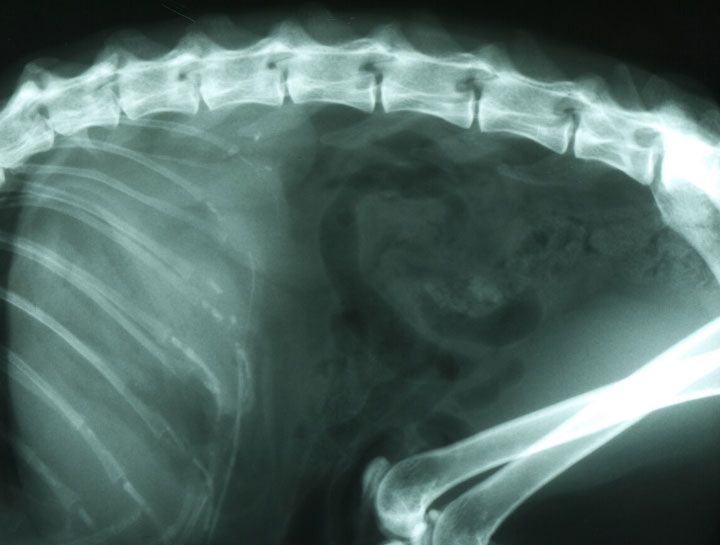

Diagnostic imaging allows us to examine your pet’s internal organs and body systems to better diagnose their conditions. There are different types of diagnostic imaging and the type your pet needs will depend on their symptoms and the affected area of the body.

Pet Digital Radiology

Digital x-rays assist in diagnosing illness & injury.